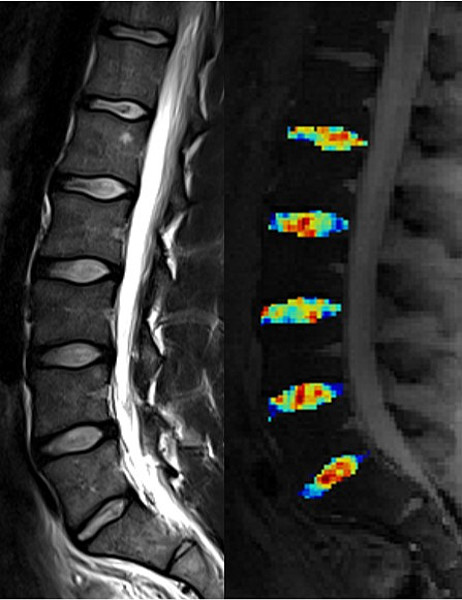

• Strukturelle und kompositionelle (molekulare) Bildgebung des Knorpels (dGEMRIC, T2-Mapping, T2* Mapping, Natrium, gagCEST)